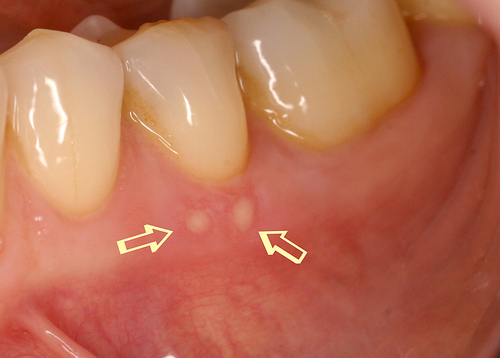

Cette biostimulation qui peut durer plusieurs minutes aboutit en général à une guérison très rapide et indolore des ulcérations gingivales (fig. 22)

Fig.22

Cicatrisation en quelques jours